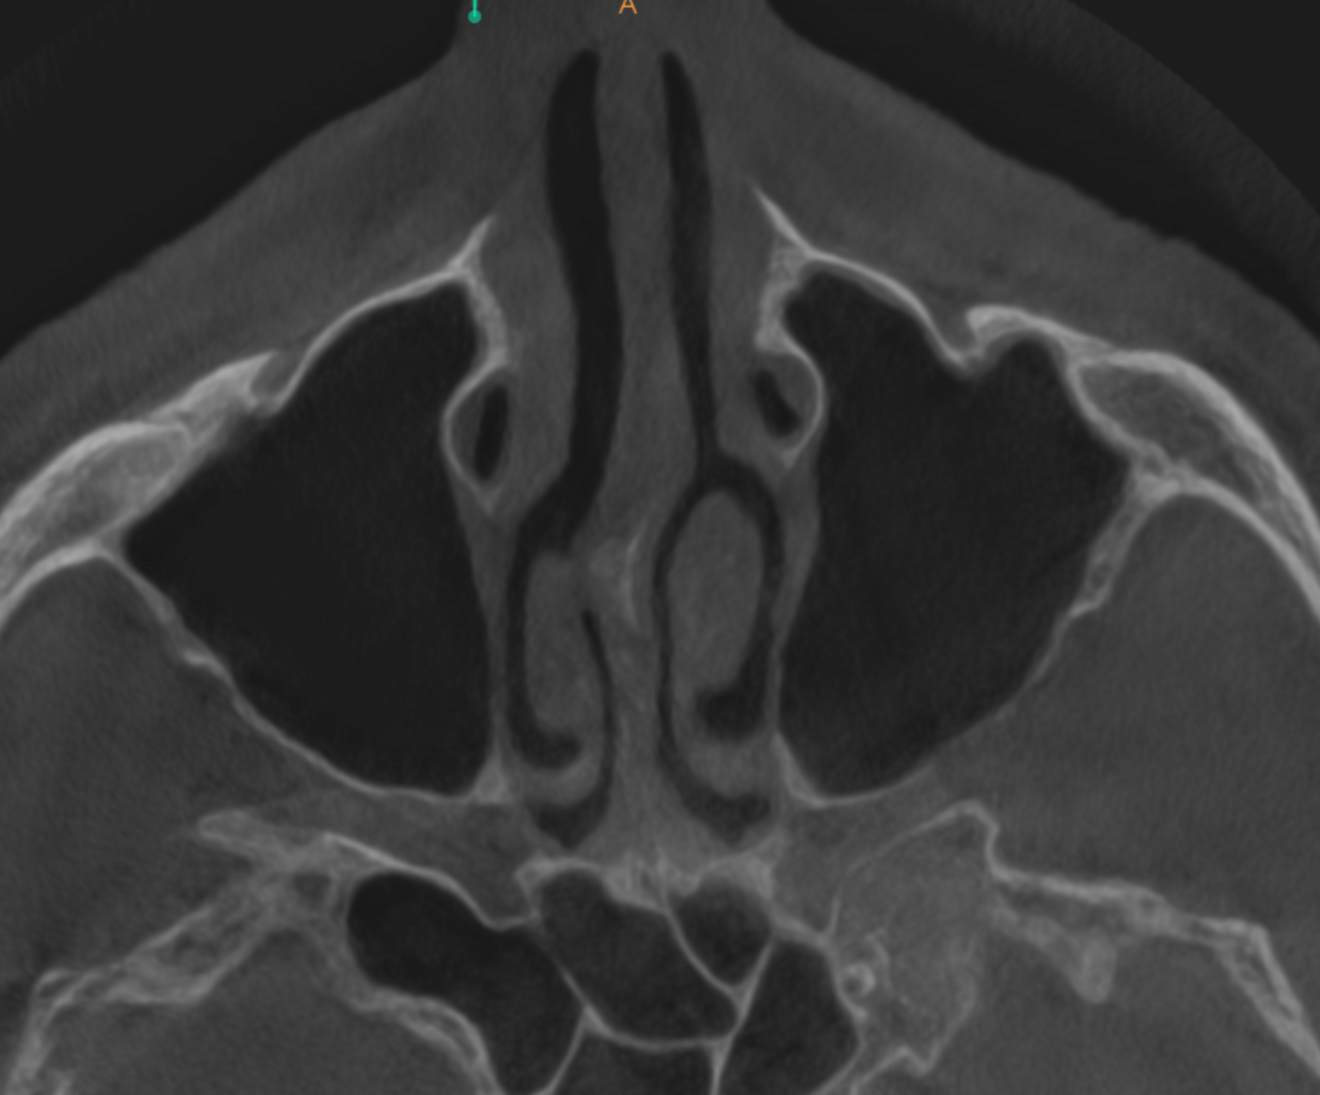

Fig. 5e: High-level transversal cross-section of the maxilla showing involvement of the sphenoid and ethmoid sinuses.

Fig. 5f: Very high-level transversal cross-section of the maxilla showing involvement of the lower part of the cavernous sinus.

The extent of the inflammation was shocking (Figs. 2a & b). Not only the maxillary sinus (Fig. 3) but the ethmoid and sphenoid sinuses too were involved, and the inflammation had spread towards the right cavernous sinus as well (Fig. 4). At this point, extraction may have been the first choice for most dental clinicians, but we had to keep in mind that invasive treatment may have increased the risk of cavernous sinus thrombosis, a potentially avoidable possibility. There are very few circumstances under which a dental procedure can cause very severe or even lethal consequences, but this case approached such a situation.

As a first step, we informed the patient about our findings on the new CBCT scan and explained the severity of his dental condition and paranasal sinusitis (Figs. 5a-f). We immediately referred him to a hospital otolaryngology department for microbial examination and proper antibiotic treatment. After nine days of a high-dose amoxicillin and clavulanic acid therapy, the endodontic treatment could be started.